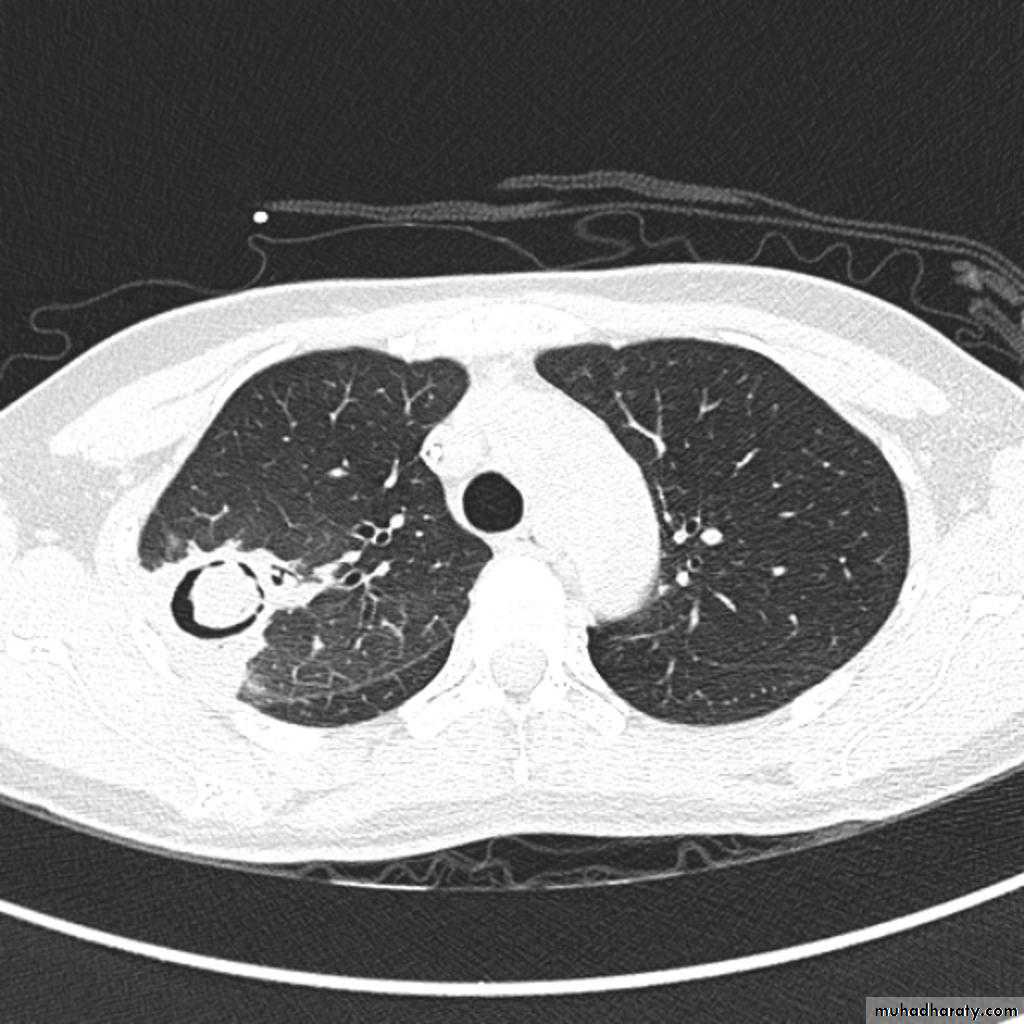

Bronchiactasis

Bronchiectasis refers to abnormal dilatation of the bronchial tree and is seen in a variety of clinical settings. CT is the most accurate modality for diagnosis. It is largely considered irreversibleCauses of bronchiactasias very important to consider

Plain radiograph

Chest x-rays are usually abnormal

1. Tram-track opacities are seen in cylindrical bronchiectasis, and

2. air-fluid levels may be seen in cystic bronchiectasis.

Honey comb shadow

3.Overall there appears to be an increase in bronchovascular markings, and bronchi seen end on may appear as ring shadows .

4.Pulmonary vasculature appears ill-defined, thought to represent peri bronchovascular fibrosis .